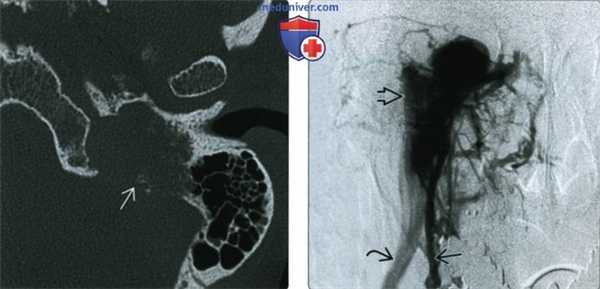

(Слева) При КТ левой височной кости в аксиальной проекции определяется параганглиома яремного гломуса; видны типичные инфильтративнодеструктивные изменения окружающей кости. Вероятно, больной предъявляет жалобы на пульсирующий шум в ухе, а за барабанной перепонкой визуализируется объемное образование красного цвета.

(Справа) При селективной ангиографии восходящей глоточной артерии в передне-задней проекции определяется интенсивное заполнение параганглиомы яремного гломуса контрастным агентом. Обратите внимание на раннее заполнение дренирующей вены через артериовенозные шунты. Часто для контроля кровопотери перед хирургическим вмешательством выполняется эндоваскулярная эмболизация.